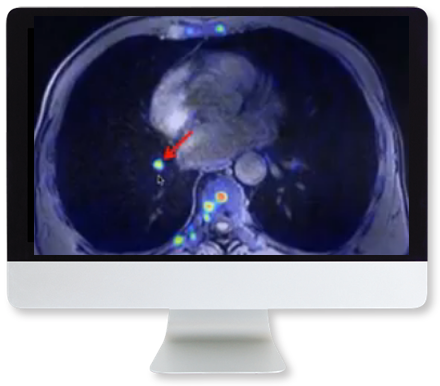

Early on, CT may be positive when the CXR is negative. The typical GGO distribution is similar, but usually more extensive than on CXR (Fig. 3).

Follow-up of established disease: On CXR and CT, GGOs and focal area of consolidation often progress and may evolve into a bilateral acute respiratory distress syndrome-like pattern when cytokine storm develops. Less common CT findings include dilated peripheral pulmonary vessels, adenopathy, rounded infiltrates, and signs of bronchial inflammation. Hospital-acquired bacterial pneumonia may complicate COVID-19 and vice versa. Preexisting lung disease (e.g., chronic obstructive pulmonary disease, interstitial lung disease, etc.) further complicate interpretation. Clearing usually starts after 2 weeks.

COVID-19 may cause hypercoagulability, leading to an increased incidence of both emboli and in situ thrombi and deep vein thrombosis.